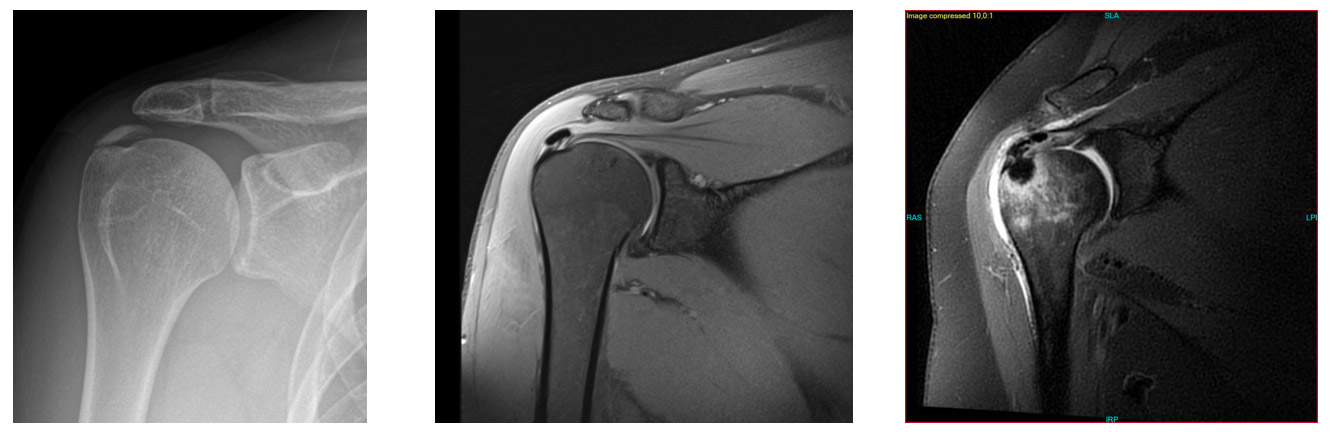

Kalsifik tendinit, sıkça karıştırıldığı tendinit (tendon iltihabı) veya bursit (bursa iltihabı) gibi durumlardan farklıdır. Klasik tendinitte, tendon iltihaplanır ancak kalsiyum birikimi söz konusu değildir. Kalsifik tendinit ise, hem iltihaplanma hem de kalsiyum birikimi içerdiği için daha karmaşık ve ağrılı bir süreçtir. Doğru teşhis için ultrason veya röntgen gibi görüntüleme yöntemlerine başvurmak şarttır.

- Kalsifik Dönem: Bu evre, kalsiyum tuzlarının tendon dokusu içinde birikmeye başladığı dönemdir. Röntgen veya ultrasonografide tebeşir tozu kıvamında beyaz alanlar görülür. Bu birikimler, omuzda ağrı, hassasiyet ve kolu hareket ettirmede zorluk gibi belirtilere yol açar. Ağrı, özellikle geceleri artabilir.

Barbotaj işlemi, bir klinikte veya poliklinik ortamında, genellikle bir ortopedi veya fizik tedavi uzmanı tarafından uygulanır. İşlem, ultrason rehberliğinde gerçekleştirilir, bu da tedavi eden hekimin kalsifikasyonun tam yerini ve büyüklüğünü net bir şekilde görmesini sağlar.

- Görüntüleme ve Lokalizasyon: Hasta uygun pozisyonda yatarken, ultrason cihazı ile omuz bölgesi incelenir. Kalsifik birikimlerin yeri, boyutu ve derinliği belirlenir. Bu, işlemin hassas ve güvenli bir şekilde yapılması için kritik bir adımdır.